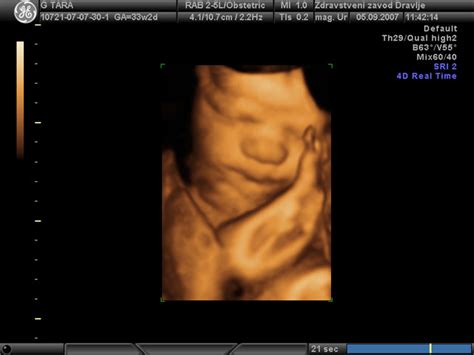

Medenična vstava, znana tudi kot medenična lega, pomeni, da otrok med porodom ni obrnjen z glavo naprej. Obstaja več vrst medenične vstave: čista medenična vstava, kjer ima otrok iztegnjene noge navzgor; trtično-stopalna lega, kjer ima otrok ukrivljena kolena in stopala prekrižana; ter popolna stopalna lega, kjer ima otrok iztegnjene noge. Poleg teh obstaja še prečna lega ploda, kjer otrok v maternici leži bočno.

Najpogostejši položaj otroka je glava navzdol, saj ta položaj omogoča najlažji porod, saj glava utira pot za ostale dele telesa. V primeru medenične vstave pa je postopek poroda nekoliko bolj naporen. Otrok se mora s trtico prilagoditi porodnemu kanalu. Ko je ritka zunaj, glava zdrsne v medenični obroč. Ker je ta obroč tesen, lahko pritiska na popkovino, kar bi lahko zmanjšalo dobavo kisika. Zato se takšen porod v zadnji fazi pogosto pospeši.

V primeru medenične vstave se zdravniki najprej odločijo za poskus zunanjega obrata. Ta postopek poteka pod ultrazvočnim nadzorom, s katerim se preveri lega otročka, njegova velikost, teža, količina plodovnice ter velikost in prostornina materine medenice. Zunanji obrat je običajno lažji pri ženskah, ki so že rodile, zaradi večje in prožnejše maternice. Uspešnost zunanjega obrata je približno 50-odstotna.